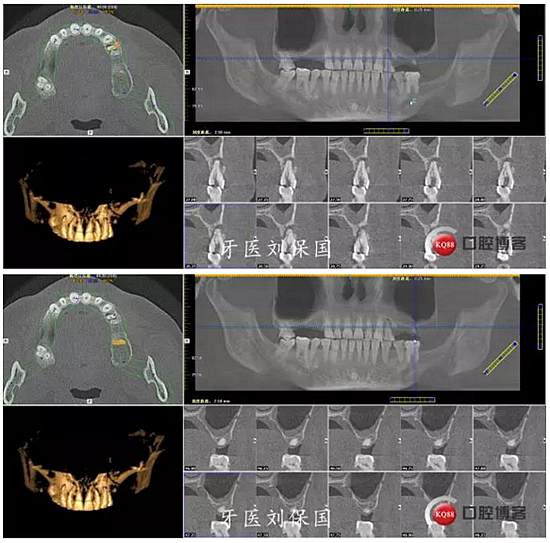

1.術(shù)前CT: